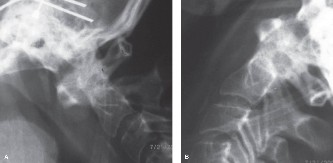

Pre-Operative Planning, Templating, and Patient Positioning

When surgical intervention becomes unavoidable, meticulous pre-operative planning is the cornerstone of a successful outcome. Advanced imaging is non-negotiable. An MRI with and without gadolinium contrast is the gold standard for defining the extent of the epidural abscess, the degree of neural compression, and the involvement of adjacent paraspinal musculature (e.g., psoas abscess). T1-weighted images typically show hypointense signals in the infected marrow, while T2-weighted and STIR sequences reveal hyperintense fluid and edema in the disc space and vertebral bodies. Gadolinium enhancement highlights the vascularized inflammatory phlegmon and the capsule of any abscesses.

In addition to MRI, a fine-cut computed tomography (CT) scan is essential for evaluating bony destruction. CT allows the surgeon to assess bone stock for pedicle screw purchase and to template the size of the interbody cages required for anterior column reconstruction. Upright standing radiographs (if the patient can tolerate them) or full-length supine films are necessary to evaluate global spinal alignment and regional kyphosis.